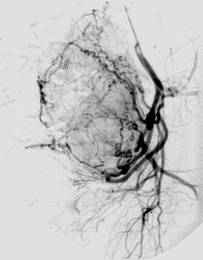

Bei der interventionellen Therapie erfolgt durch Embolisation (Einschwemmung von kleinen Kunstpartikeln) die Verödung von Myomen. Dazu wird nach örtlicher Betäubung durch einen Radiologen ein Katheter in die Leistenarterie eingebracht, über den winzige Kügelchen in das Myom eingeschwemmt werden, die dafür sorgen, das die Blutzufuhr zum Myom unterbunden wird. Innerhalb von drei bis sechs Monaten schrumpfen die Myome bis auf ca. die Hälfte ihrer Ausgangsgröße. Diese Methode kann also vorteilhaft für Frauen sein, deren Familienplanung zwar abgeschlossen ist, die aber einen Organerhalt wünschen.